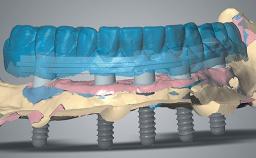

Immediate Loading of an Anterior Implant with a Prefabricated Crown

A fully digital workflow for a patient with adequate bone but soft tissue defects is outlined in this case. Key features include: Use of the CAD software’s mirroring feature to create the digital diagnostic wax-up, a CAD/CAM custom zirconia abutment and PMMA provisional crown, connective-tissue grafting performed at the time of implant placement, and modification of the provisional crown to shape the emergence profile and change the position of the labial mucosal margin to better match the contralateral tooth.